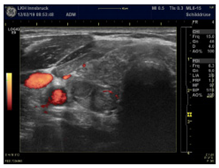

| Slight increase with a point-like pattern—suggests magnesium deficiency | |

| Moderate increase with a wire-like pattern—suggests CoQ10 deficiency | |

| Very intense hyper-perfusion—suggests a severe combined deficiency condition | |

| Power Doppler Images | ![]() | ![]() | ![]() |

| Condition | Magnesium def. pattern | CoQ10 def. pattern | Chronic fibrosis |